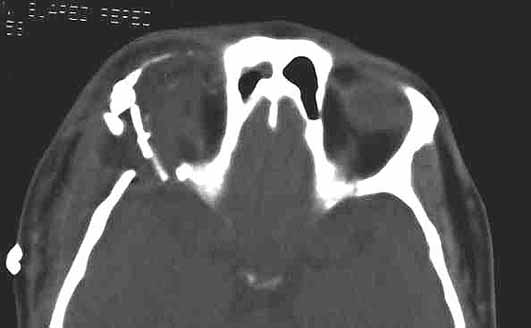

Fig. 3.CT efectuada tras la intervención en la que se observa la resección completa de la lesión y la reconstrucción de la pared lateral y el techo de la órbita derecha. |